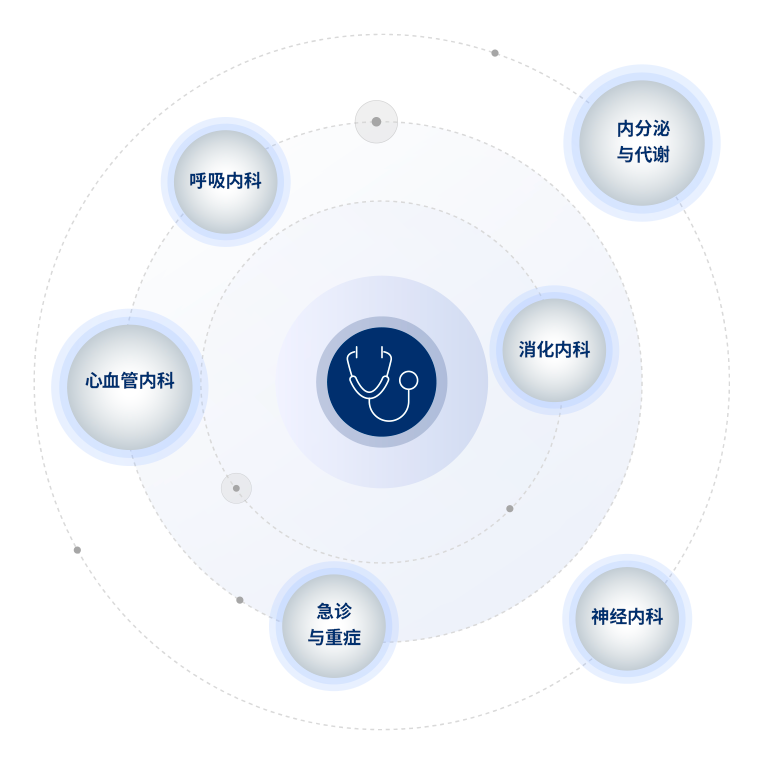

- 內(nei)科(ke)中(zhong)心重(zhong)點打造(zao)科(ke)室

-

心血筦(guan)內(nei)科(ke)

神經(jing)內(nei)科(ke)

消化內(nei)科(ke)

呼吸(xi)內(nei)科(ke)

內(nei)分(fēn)泌與代(dai)謝(xiè)